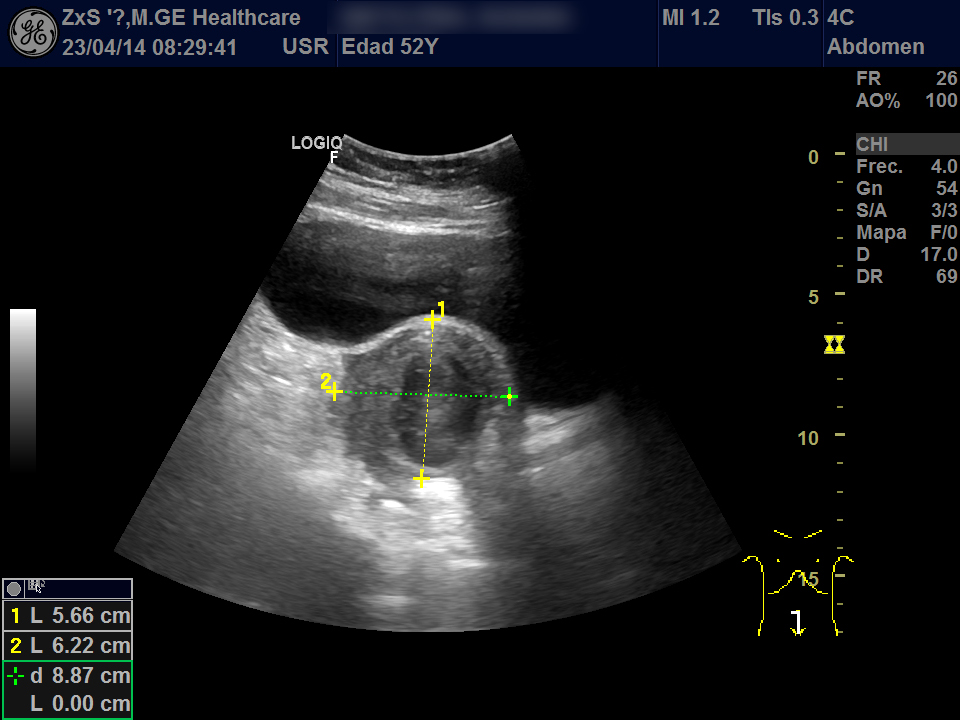

Hígado de bordes lisos y ángulo agudo, aspecto heterogéneo, no se observan LOES. Vía biliar extra e intrahepática no dilatada. Vesícula poco replecionada sin imágenes en su interior, Murphy ecográfico negativo. Ambos riñones de localización y tamaño normal. Buena diferenciación córtico-sinusal y en riñón derecho discreto aumento del tamaño de la pelvis renal compatible con hidronefrosis grado 2. Vejiga bien replecionada sin ecos en su interior. Se objetiva útero de tamaño normal con una imagen hiperecogénica que corresponde a DIU y en la zona derecha una lesión redondeada de aproximadamente 5,5 x 6,5 de diámetro de contenido heterogéneo que dudamos si puede corresponder a masa ovárica desconocida. Se deriva al hospital por sospecha de masa ovárica.

Evolución y seguimiento: Urgencias hospital TAC abdominal: en región anexial lesión de aspecto sólido-quístico de 6,5 x 5,5 cm con cambios inflamatorios de la grasa adyacente y que produce leve desplazamiento del útero hacia la izda. No se observan colecciones, neumoperitoneo, ni líquido libre intraabdominal.

Dco hospital: Absceso tubo-ovárico Ingreso. Se retira DIU y se pauta tto antibiótico IV. Posterior laparoscopia abierta: Plastrón inflamatorio que alberga trompa y anejo derecha íntimamente adherido a asas intestinales, útero y pared pélvica.